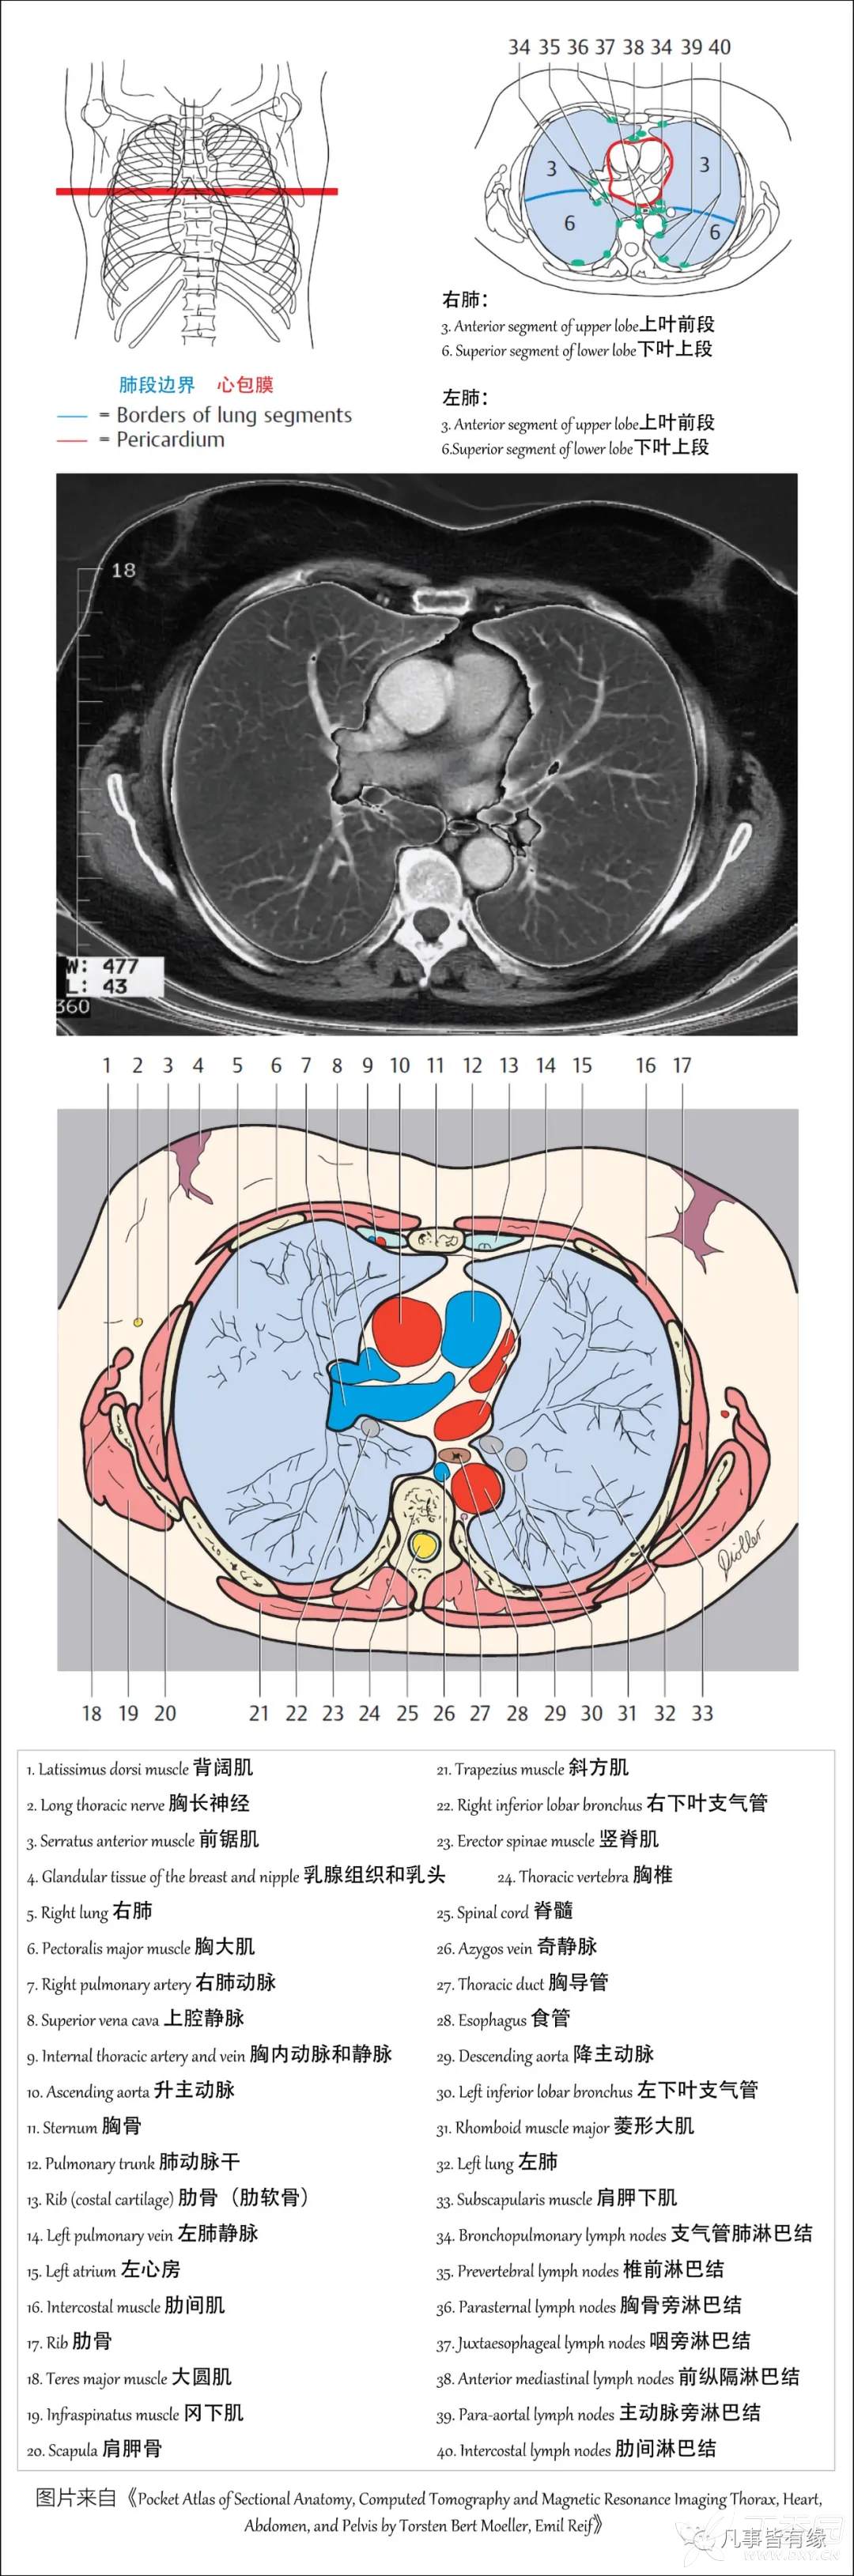

(一)胸部CT轴位断层解剖: